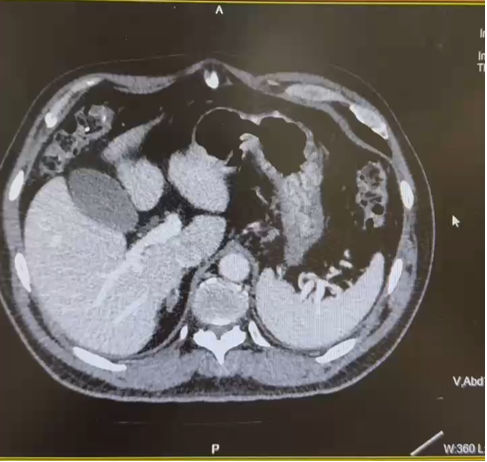

CT:1. 右肾癌伴右肾静脉受累,侧支循环形成;2. 右肾上腺结合部结节灶,转移可能;3. 右输尿管上段管壁局部增厚:侵犯?4. 左肾囊肿。

PETCT:1. 右肾中-下份混合密度软组织肿块,糖代谢轻度升高,SUVmax6.4, 右肾内糖代谢稍增高灶,SUVmax3.8,右肾癌合并肾静脉瘤栓形成;2. 右肾上腺结合部低密度灶,糖代谢轻度增高,转移瘤,SUVmax3.1。

CT(2022.7):1. 右肺转移瘤切除术后改变;2. 左肾上腺结节,转移?3. 左肾多发结节,转移瘤?4. 腹膜后淋巴结肿大,转移可能;5. 左肾多发小囊肿。

PETCT(2022.10):1. 左侧肾上腺结节灶,糖代谢增高,转移瘤可能性大;2. 左肾多发结节状突起,糖代谢增高,考虑转移瘤,需结合增强 CT 综合判断;3. 右下肺切除术后,术区未见复发;4. 右侧胸壁局部增厚、糖代谢增高,术后改变?建议追踪。

CT(2023.7.17):1. 左肾上腺结节、左肾结节及肿块较前明显增大:转移?左肾 CA 并左肾内、肾上腺转移?2. 腹膜后淋巴结较前增大,转移可能;3. 余况基本同前。

CT(2023.12.6):1. 左肾上腺结节较前稍缩小、左肾结节及肿块较前稍缩小;2. 腹膜后淋巴结转移灶同前;3. 余况基本同前。